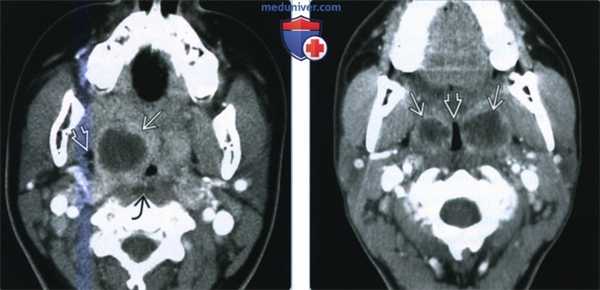

КТ с контрастированием: левосторонний паратонзиллярный абсцесс. Образование имеет гипоинтенсивный центр, окруженный усиленной стенкой. Отек левой нёбной миндалины и слизистой глотки на стороне поражения вызывает асимметричное сужение глотки. Рот остается открытым в связи с болевым синдромом.

КТ с контрастированием (реконструкция во фронтальной плоскости): левосторонний паратонзиллярный абсцесс. Выявляется перифокальный отек и повышенная плотность слизистой, а также асимметричное сужение ротоглотки, распространяющееся в дистальном направлении слева от мягкого нёба. В абсцессе наблюдается типичное периферическое усиление с гипоинтенсивной полостью в центре.